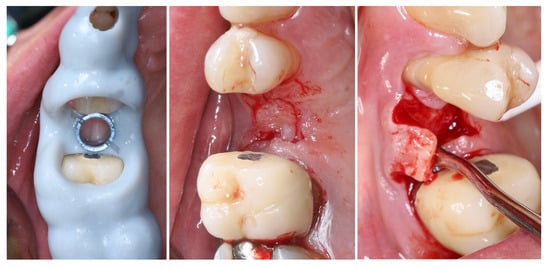

Intraoperatively, the flap preparation included (Figure 7) crestal flap preparation by marking the borders of the implantation area through the surgical guide with the tissue punch followed by crestal U-shaped incision with the blade (15C) perpendicular to crestal mucosa.

Figure 7.

Flap design and flap reflection.

The preservation of unprepared areas of the crestal soft tissue to the adjacent teeth, transformed them into the future peri-implant papillae that can be used to ensure stable primary flap closure, protecting the peri-implant bone from post-surgical resorption.

The U-shaped incision was extended mesially and distally with oblique incisions at the border of the crestal roll flap, separating the peri-implant papillae into anatomic (unprepared part) and surgical parts. The crestal part of the flap was de-epithelized with a 15C blade and microsurgical scissors and was elevated to full thickness with a periodontal chisel (36/37 Rhodes Back-Action chisel, Hu-Friedy, Chicago, IL, USA).

The buccal flap is prepared in partial thickness with the two incisions known from mucogingival surgery, described by De Sanctis and Zucchelli, a split-thickness incision, with the blade parallel to the bone, keeping the periosteum intact, and a split-thickness incision parallel to the external mucosal surface, releasing muscle insertions from the flap. A critical aspect of the procedure was the preservation of the periosteal layer on the buccal wall of the residual socket. This minimally invasive flap design, characterized by split-thickness preparation and the absence of vertical releasing incisions, ensured sufficient vascularization of the flap and minimized the risk of scar formation on the buccal surface [25,26].